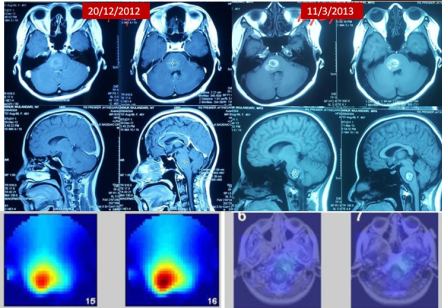

In late 2012, Bu Ninuk was diagnosed with inoperable brainstem cancer and given a life expectancy of less than six months. After being sent home from the hospital in a helpless, bedridden state because doctors could no longer offer treatment, her family turned to ECCT (Electro-Capacitive Cancer Therapy) as a final hope. Remarkably, within just one month of using the “cancer helmet,” she regained enough strength to travel to Mecca for the Umrah pilgrimage. Her recovery was so profound that she returned from the trip not in a wheelchair, but walking independently and pushing her own luggage, eventually surpassing the 10-year survival milestone.